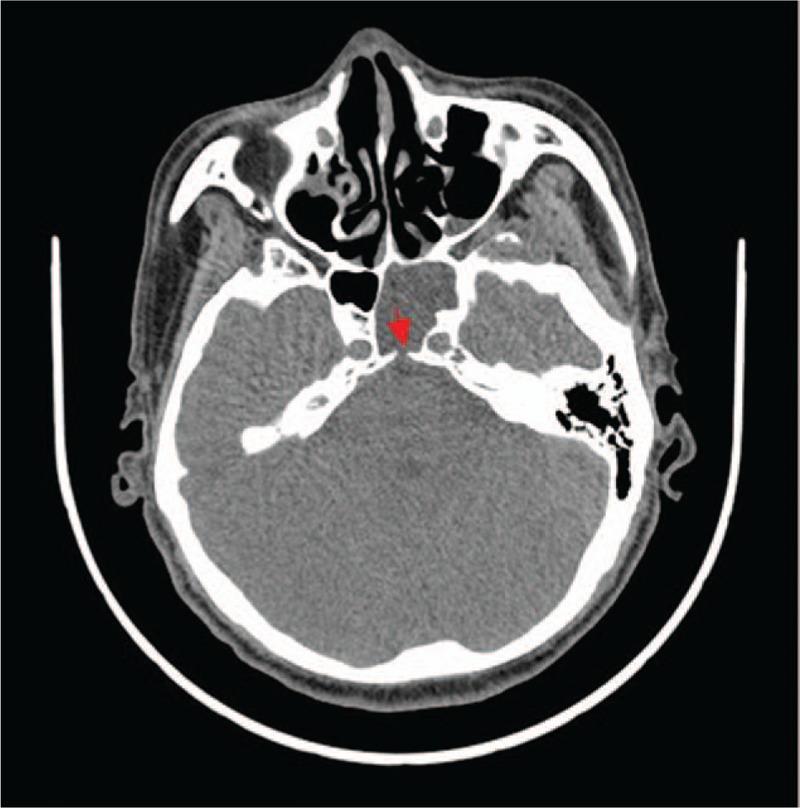

Spontaneous cerebrospinal fluid leakage is usually caused by developmental abnormalities and is rare, accounting for approximately 5% of the cases of cerebrospinal fluid (CSF) leakage. To the best of our knowledge, clival dysplasia-caused CSF rhinorrhea has never been reported in the neurosurgical field.

自发性脑脊液漏通常由发育异常引起,较为罕见,约占脑脊液漏病例的5%。据我们所知,神经外科领域从未报道过由斜坡发育异常导致的脑脊液鼻漏。